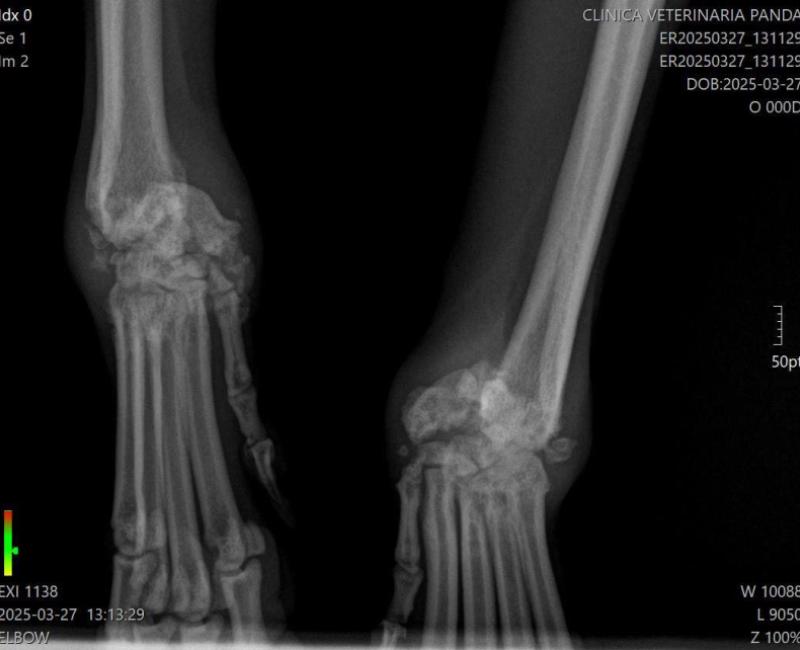

Ahora viene la segunda parte que casi es la peor que la primera: Observamos que tenía las muñecas inflamadas y andaba con dificultad. Tras varias radiografías, se observan las muñecas partidas (no reciente), y una de ellas luxada. Creen que pudieron tenerlo colgado o que lo arrastraron sujeto por las patas.